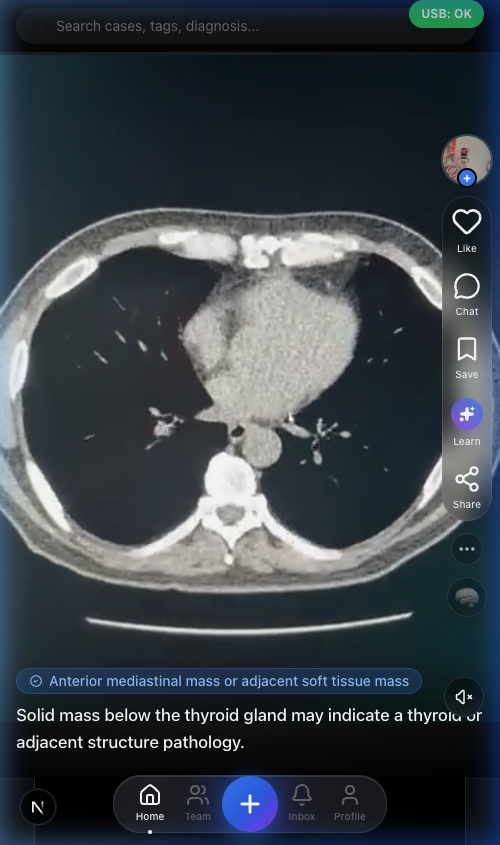

ANTR Case Feed